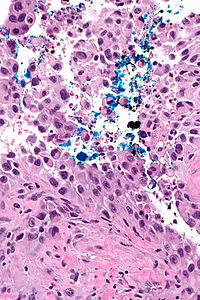

A positive surgical margin (tumour with cautery artifact) in colorectal carcinoma. H&E stain.